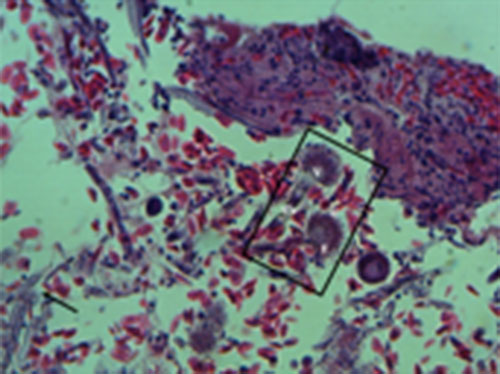

Corte histológico de pulmón teñido con hematoxilina-eosina en el que se observan hifas hialinas, septadas, con ramificación dicotómica en ángulo agudo (flecha) compatibles con aspergillus y cabezas conidiales (rectángulo) compuestos por conidios (C) fiálides (F) vesícula (V) y conidióforo (Co).

Se revisan secciones de pulmón en donde se observa abundante cantidad de estructuras micóticas alargadas, anchas, septadas y con ramificaciones dicotómicas así como moderada cantidad de células inflamatorias compuestas por heterófilos y linfocitos, así mismo se observan extensas zonas de necrosis y hemorragia.

Aspergillus es un microorganismo ubicuo por lo que la presencia de cabezas conidiales en los pulmones de esta paloma son indicativas de un alto grado de contaminación del medio ambiente así como posible inmunosupresión pues regularmente no es posible observar este tipo de estructuras en las lesiones microscópicas.